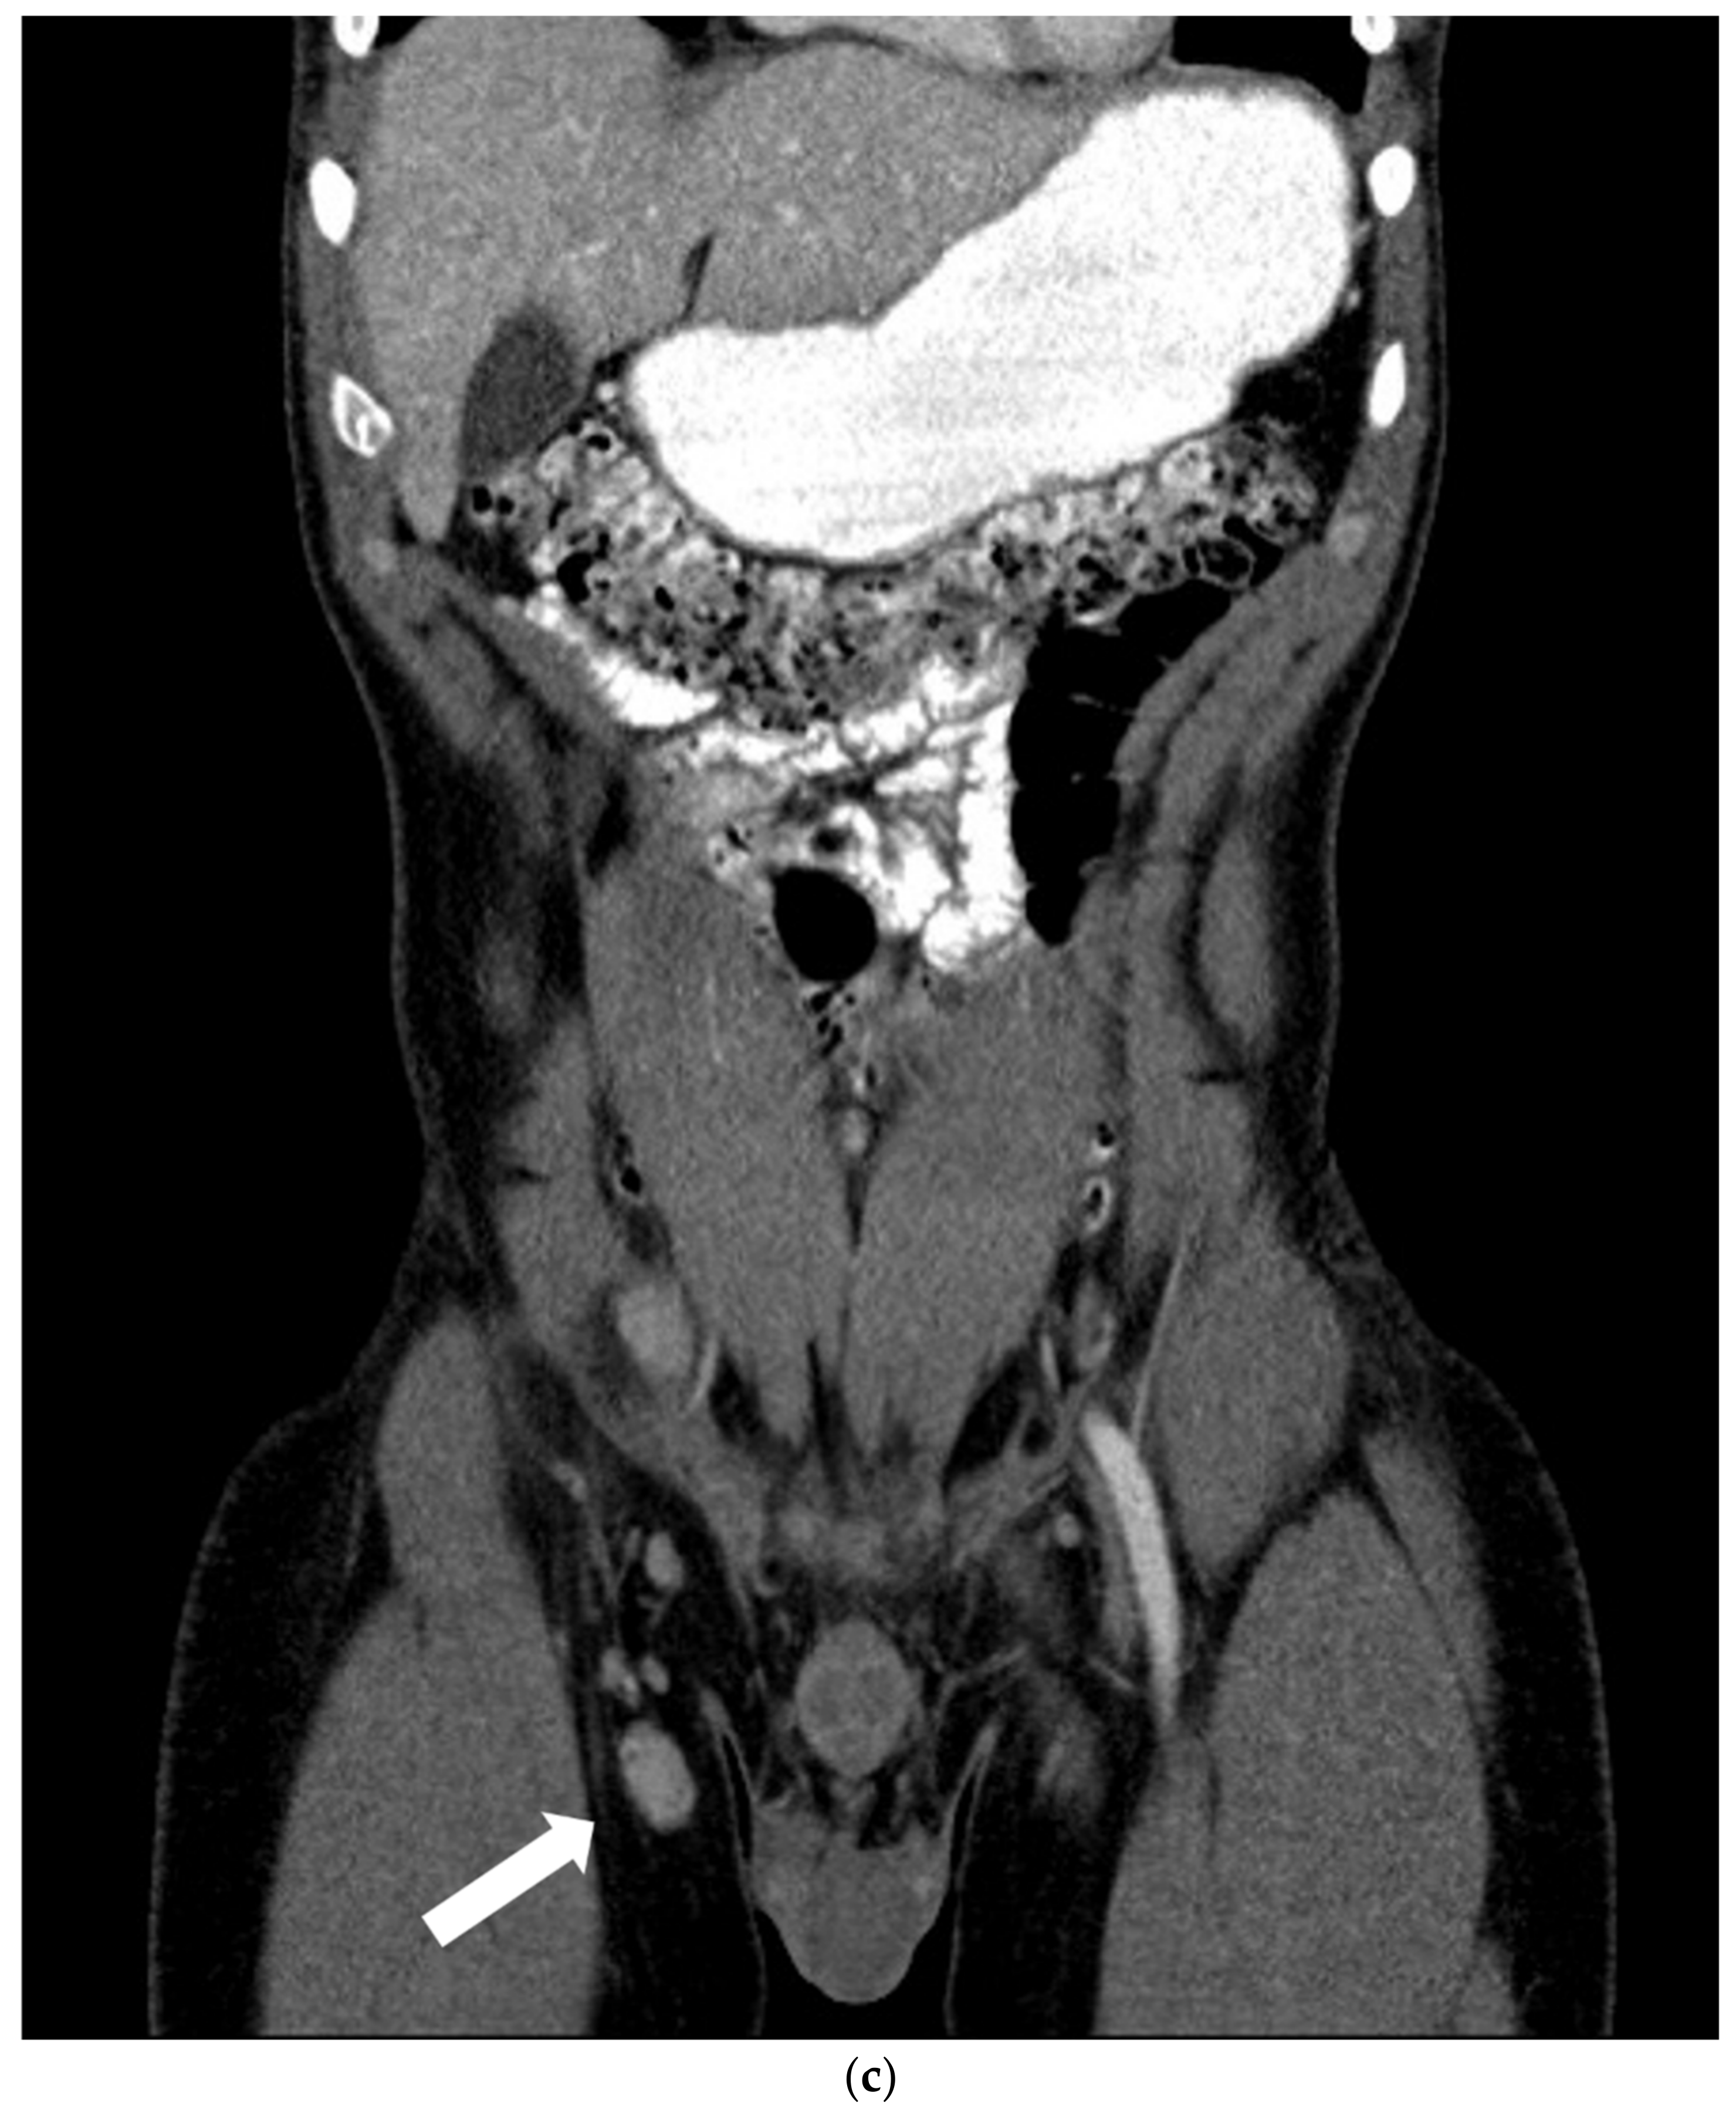

2. Case Report